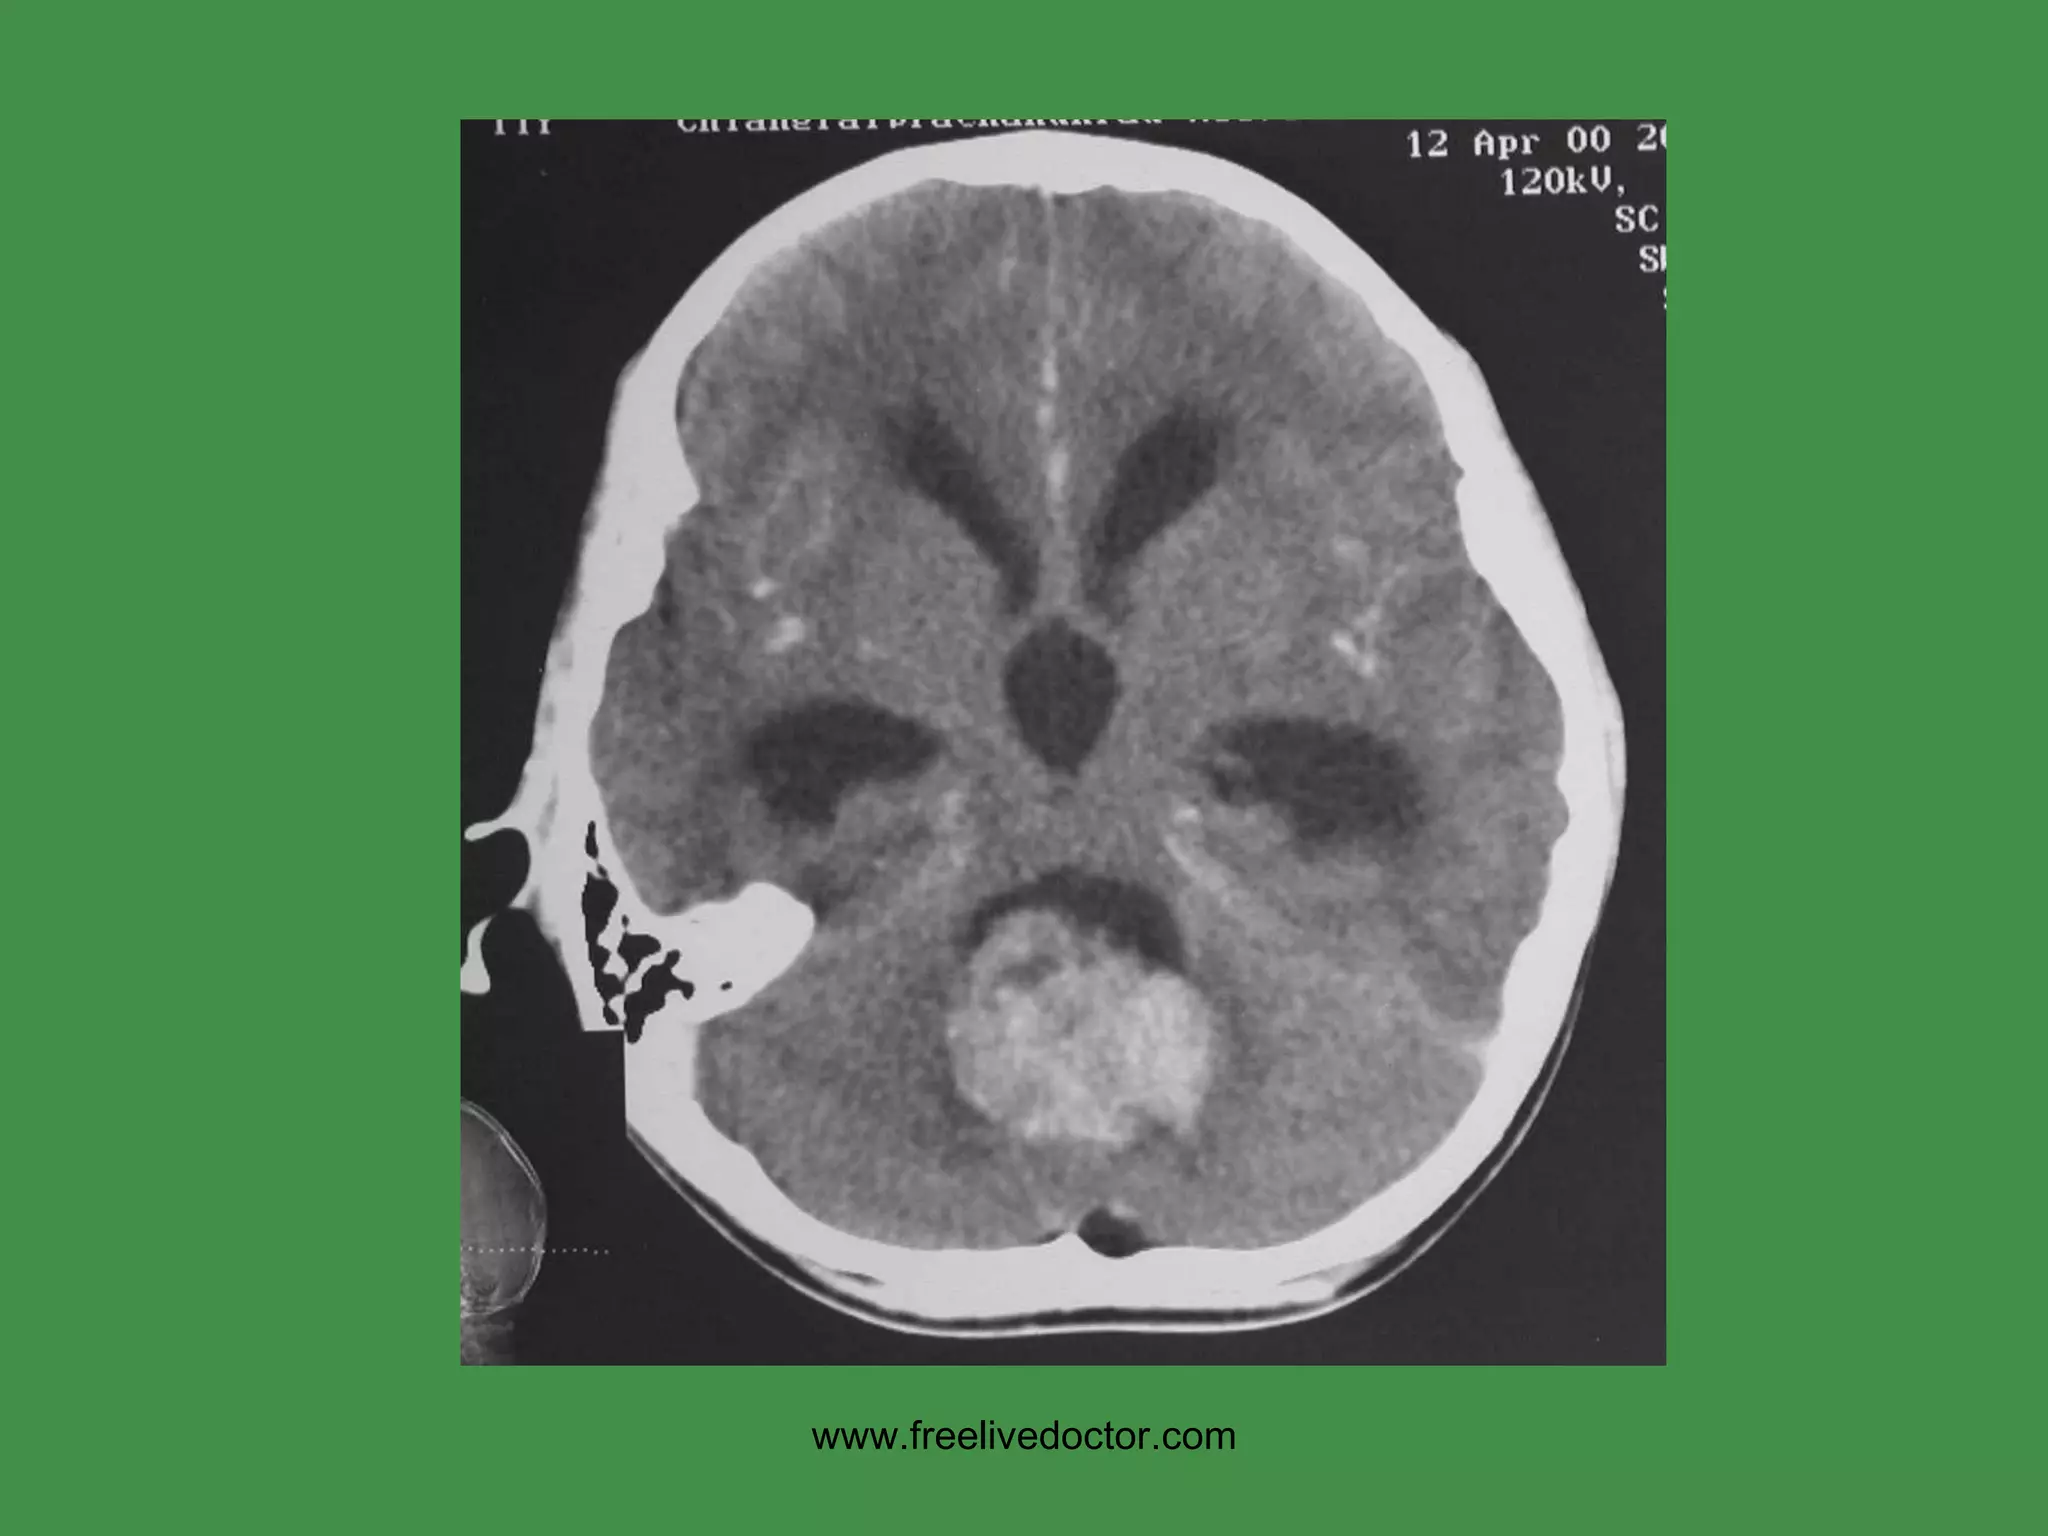

HYPERTENSIVE CVA Intracerebral Basal Ganglia Region (lenticulostriate arteries of internal capsule,  putamen) www.freelivedoctor.com

HYPERTENSIVE CVA www.freelivedoctor.com

• #71 Basal ganglia symptoms include tremors (rhythmic, involuntary, oscillatory movements), athetosis (slow, writhing movements of the fingers and hands, and sometimes of the toes), chorea (abrupt movements of the limbs and facial muscles), ballism (violent, flailing movements), and dystonia (a persistent posture of a body part which can result in grotesque movements and distorted positions of the body).